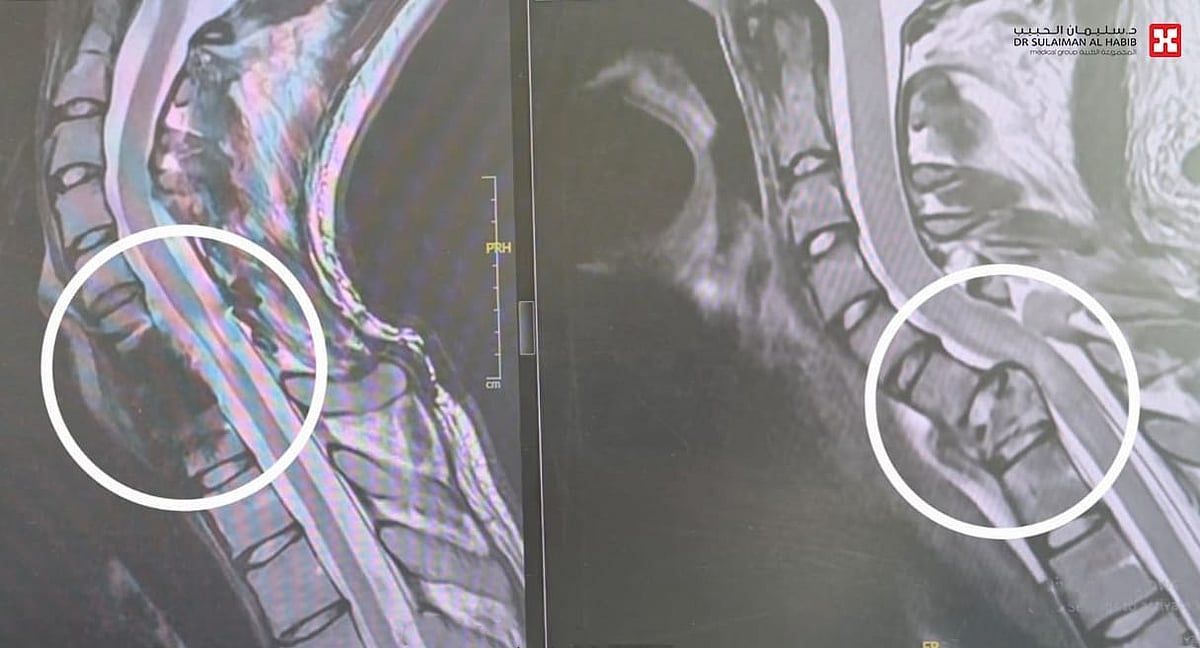

وقال د. مسعود أن المصاب وهو شاب يبلغ من العمر"24" عاماً، تلقى الاسعافات الأولية بالطوارئ ووضع على التنفس الاصطناعي مباشرة، وخضع لفحوصات دقيقة بعدما طرأ استقرار نسبي على حالته، حيث أظهرت الأشعة المقطعية Ct-scan والرنين المغناطيسي Mri وجود كسر مركب بالفقرة العنقية رقم "7"، وانزلاق غضروفي حاد وضغط على النخاع الشوكي، مع شلل في الأطراف العلوية ابتداءً من العصب رقم "7" وإلى الأسفل، وأجريت له عمليتين، تم في الأولى إزالة الفقرة العنقية السابعة المتهشمة بالكامل، والاستعاضة عنها بأخرى صناعية وتثبيتها بصفيحة وبراغي، في تدخل طبي نادر من الجهة الأمامية، وبإمكانيات كبيرة وفريق طبي متميز، واستمرت العملية لـ"5" ساعات، وأعيد إلى العناية المركزة ووضع على التنفس الاصطناعي وبعد مرور "72" ساعة وتحسن حالته، نقل إلى غرفة العمليات مجدداً، وخضع لعملية جراحية أخرى استمرت "3" ساعات، وتم فيها إزالة الكسور المتبقية خلف العمود الفقري، وكذلك تحرير النخاع الشوكي من الضغط، تثبيت العمود الفقري ببراغي وقضبان معدنية من الفقرة العنقية 5 و6، على الفقرة الصدرية 1 و2، جرى الدخول في هذه المرة من الخلف، ونقل المصاب مجدداً العناية المركزة ووضع التنفس الاصطناعي لمدة "48" ساعة أخرى، ومع تقدم حالته، قام الفريق الطبي بتخفيف التخدير والتنفس الاصطناعي تدريجياً بطريقة تسمى weaning، وبعد "72" ساعة استفاق وبدأ في تحريك يديه، وأُحِيل إلى غرفة التنويم، واستمر تحسنه إلى أن غادر المستشفى بعد أسبوعين من العملية مشياً على قدميه مع بعض المعاونة.